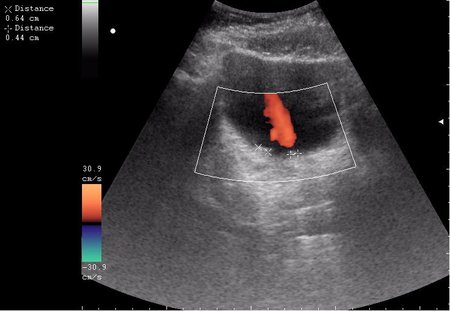

Богу богово, кесарю - кесарево (я про анализы и клинические данные). На сонограммах неубедительно продемонстрирован осадок да и стенки м.п. не утолщены.

зато какое наполнение! а осадок убедительный! а же не 7-кой смотрела!На сонограммах неубедительно продемонстрирован осадок да и стенки м.п. не утолщены.

Сравните

Продольное сканирование мочевого пузыря После легкой перкуссии мочевого пузыря